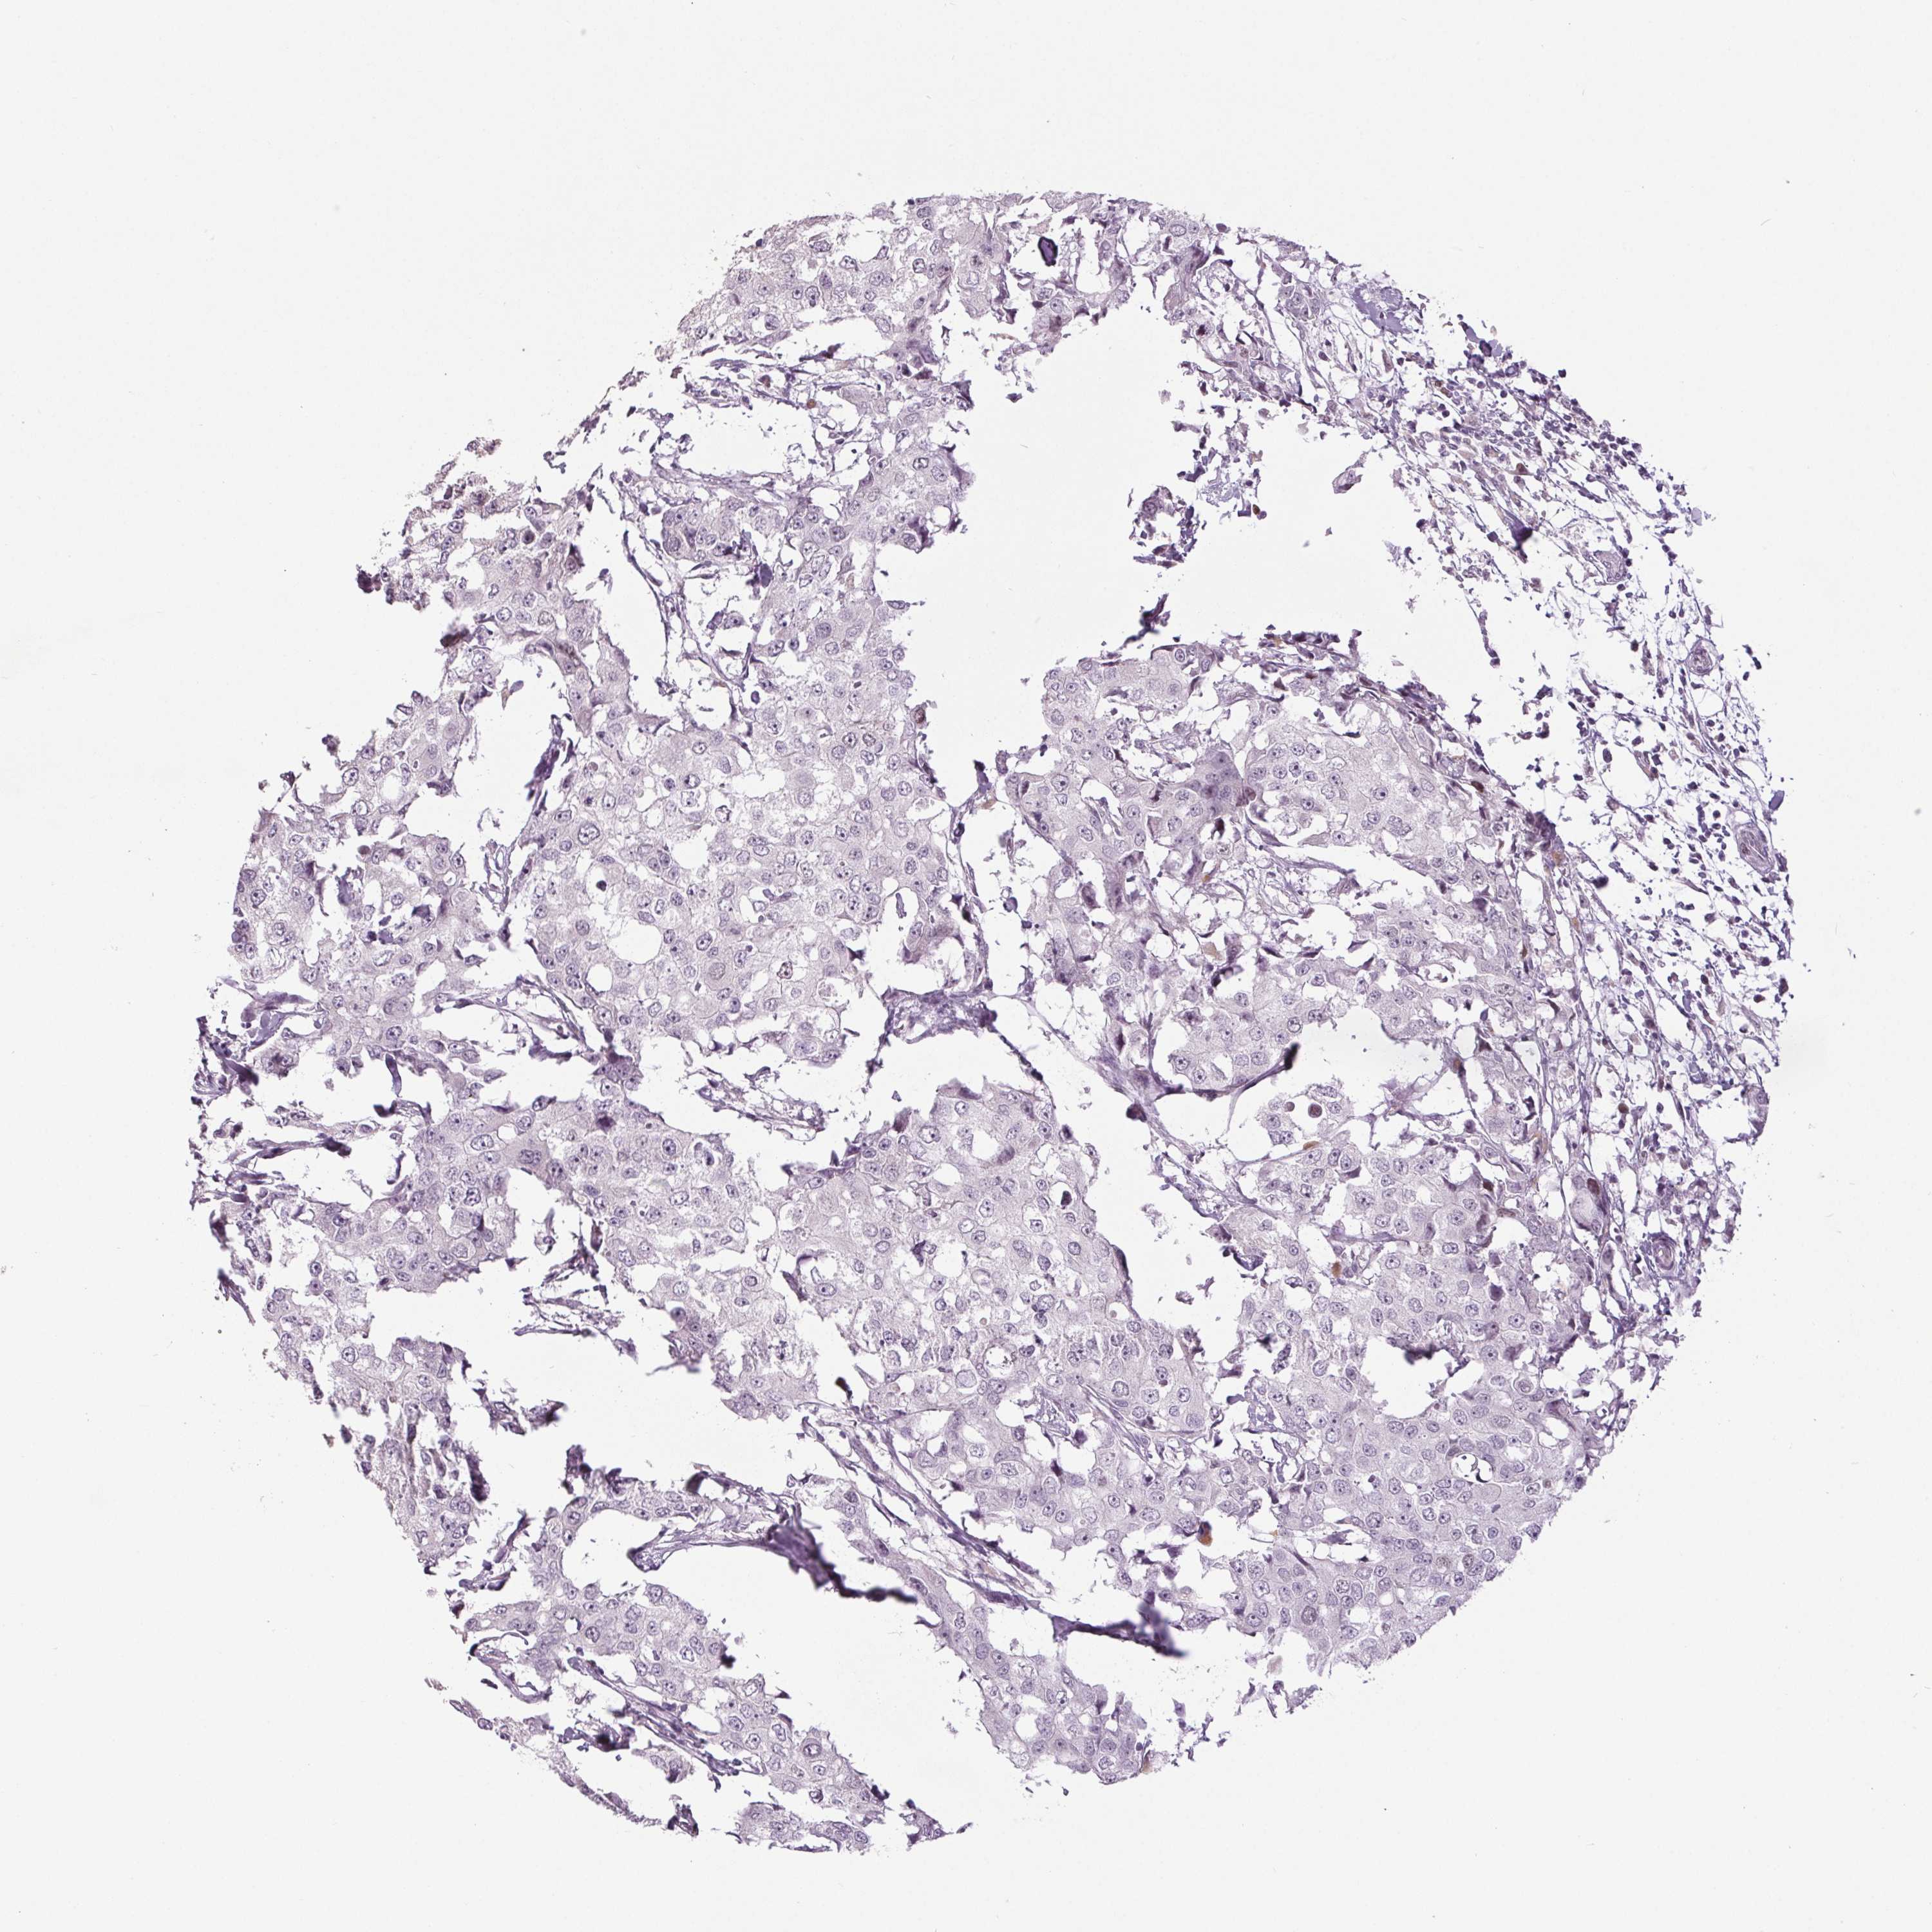

Breast cancer

Human cancer